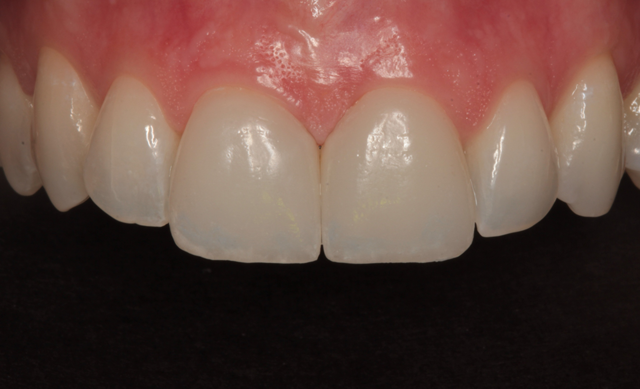

The final result is shown from the incisal view in Figure 27. The facial view after treatment can be seen in Figure 28. The patient's new smile is shown in Figure 29.

Fig. 27 Fig. 28

By using team treatment, Peter and I were able to achieve a superb color match with ceramic veneers that mimicked the appearance the surrounding neighbors. It was my job to prepare the teeth properly, acquire accurate impressions, provide excellent photography, choose a shade and deliver the finished laminates. Peter's job was to pour accurate models, produce the ceramic veneers and develop the color and contours to achieve the esthetic result.